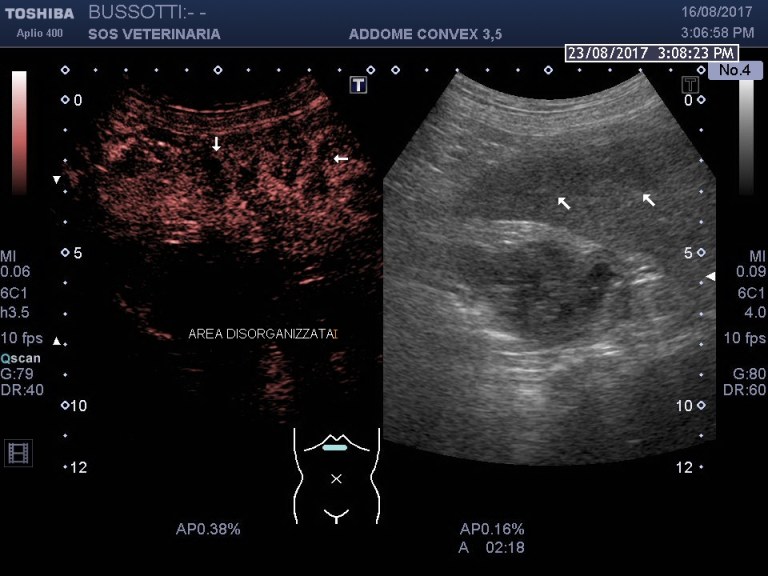

osservando la contrastografia ceus si evidenzia a livello epatico ipoenhancement anhancement delle lesioni focali tondeggianti e delle aree ventrali disorganizzate in tutte le fasi

il nodulo sul bordo splenico assume contrasto e lo dismette rapidamente rispetto al parenchima splenico rimanendo ipoenhancement

la contrastografia ,in questo caso non e’ stata essenziale per la diagnosi (l imaging in B mode era molto significativo) ma ha evidenziato la severita’ delle lesioni epatiche ,confermato la natura metastatica della malattia ,un eccezionale supporto quindi , ad una diagnosi ,fortemente sospetta che ha permesso ,in un momento non facile per il proprietario sopratutto e secondariamente per il medico curante, di prendere consapevolezza della gravita’ della malattia e accelerare l’ iter decisionale post diagnostico .